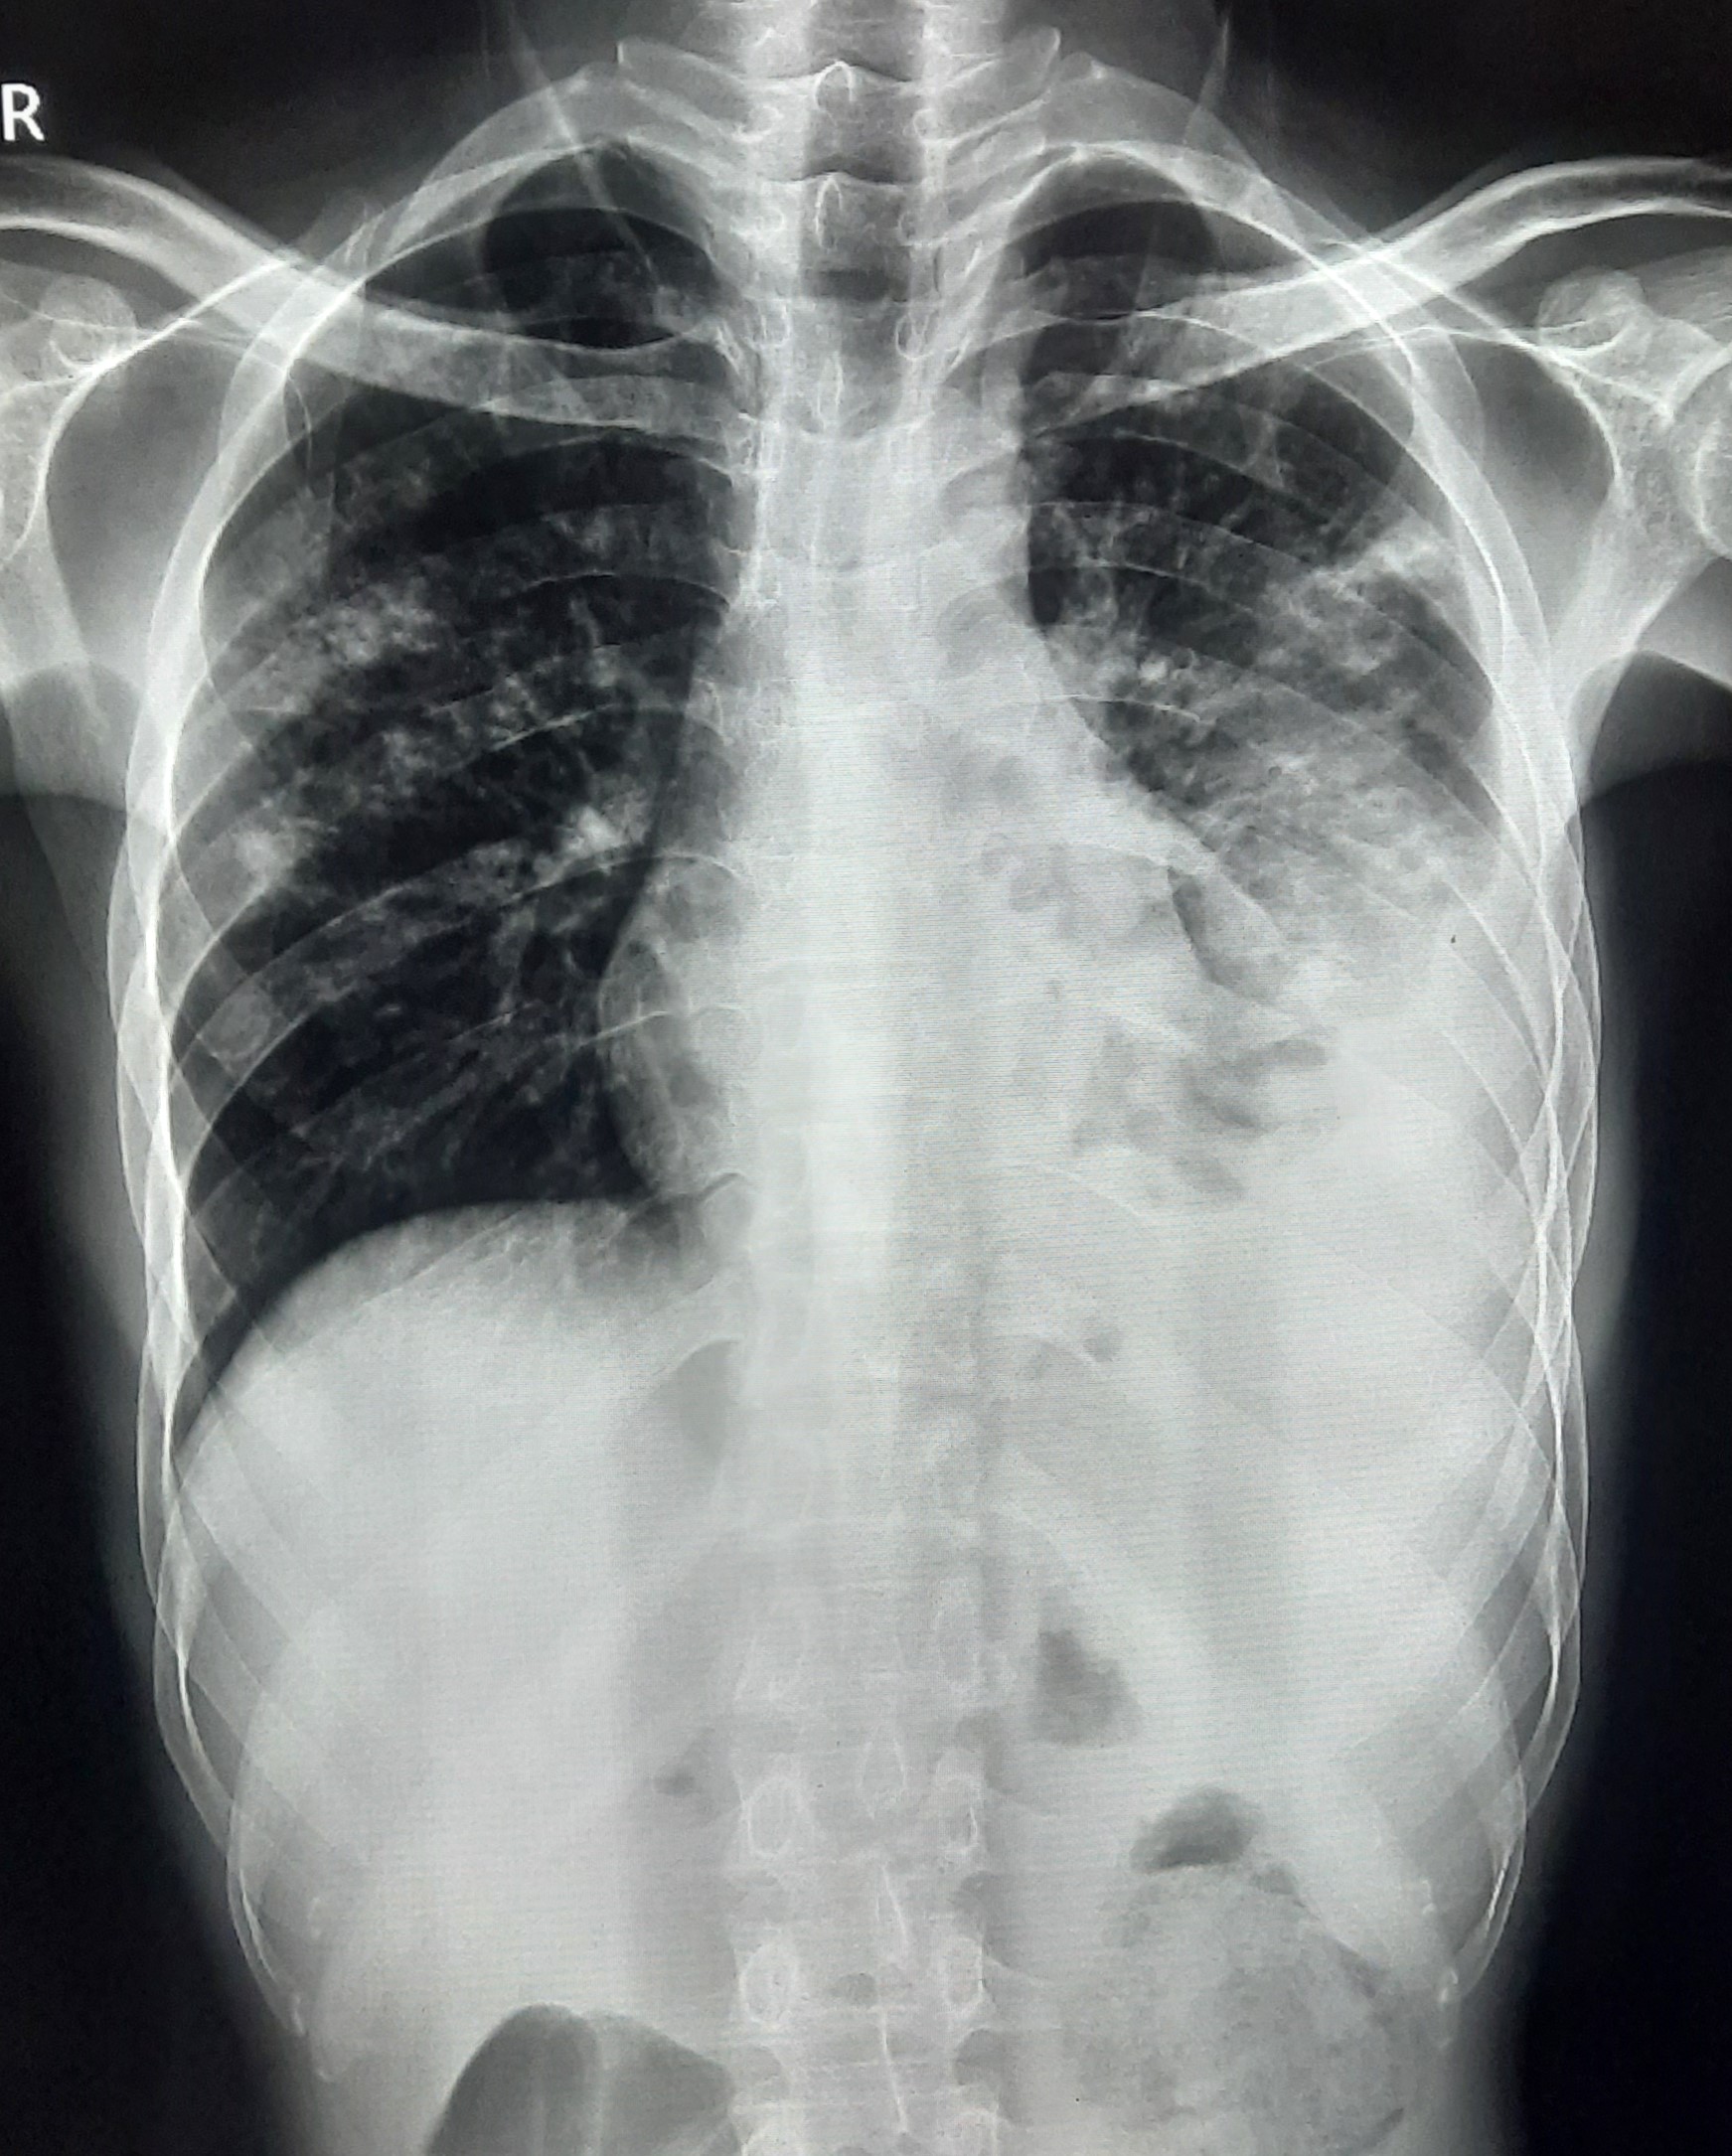

| 51 | IGGMC, Nagpur, Nagpur | P2 | 29-4421 | Santosh Neware | Consent taken on Paper | 40 Yrs. |

Provisional Diag : Pulmonary Tuberculosis

Final Diag : Pulmonary tuberculosis (Microbiologically Confirmed PTB) |

TB Case (Confirmed) | Right Upper & mid zone fibro cavitary lesion present, upward pull of right hemidiaphragm, tracheal pull right sided | Abnormality visible on x-ray |